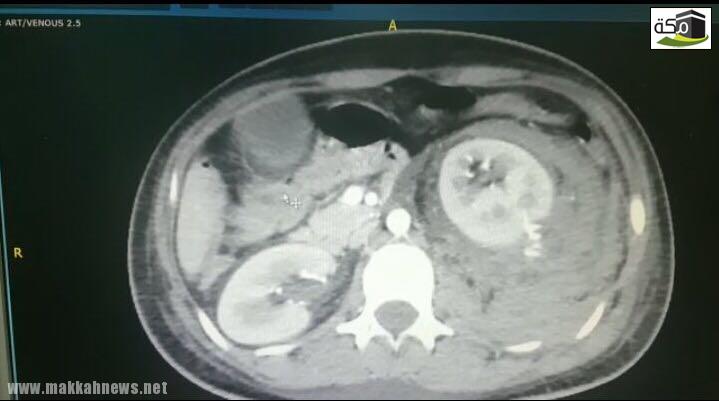

إنجاز طبي – فريق طبي ينجح في إيقاف نزيف كلوي حاد لعشرينية

تمت في مستشفى الملك فهد بالمدينة المنورة فريق طبي ينجح في إيقاف نزيف كلوي حاد لعشرينية بفضل الله نجح فريق…